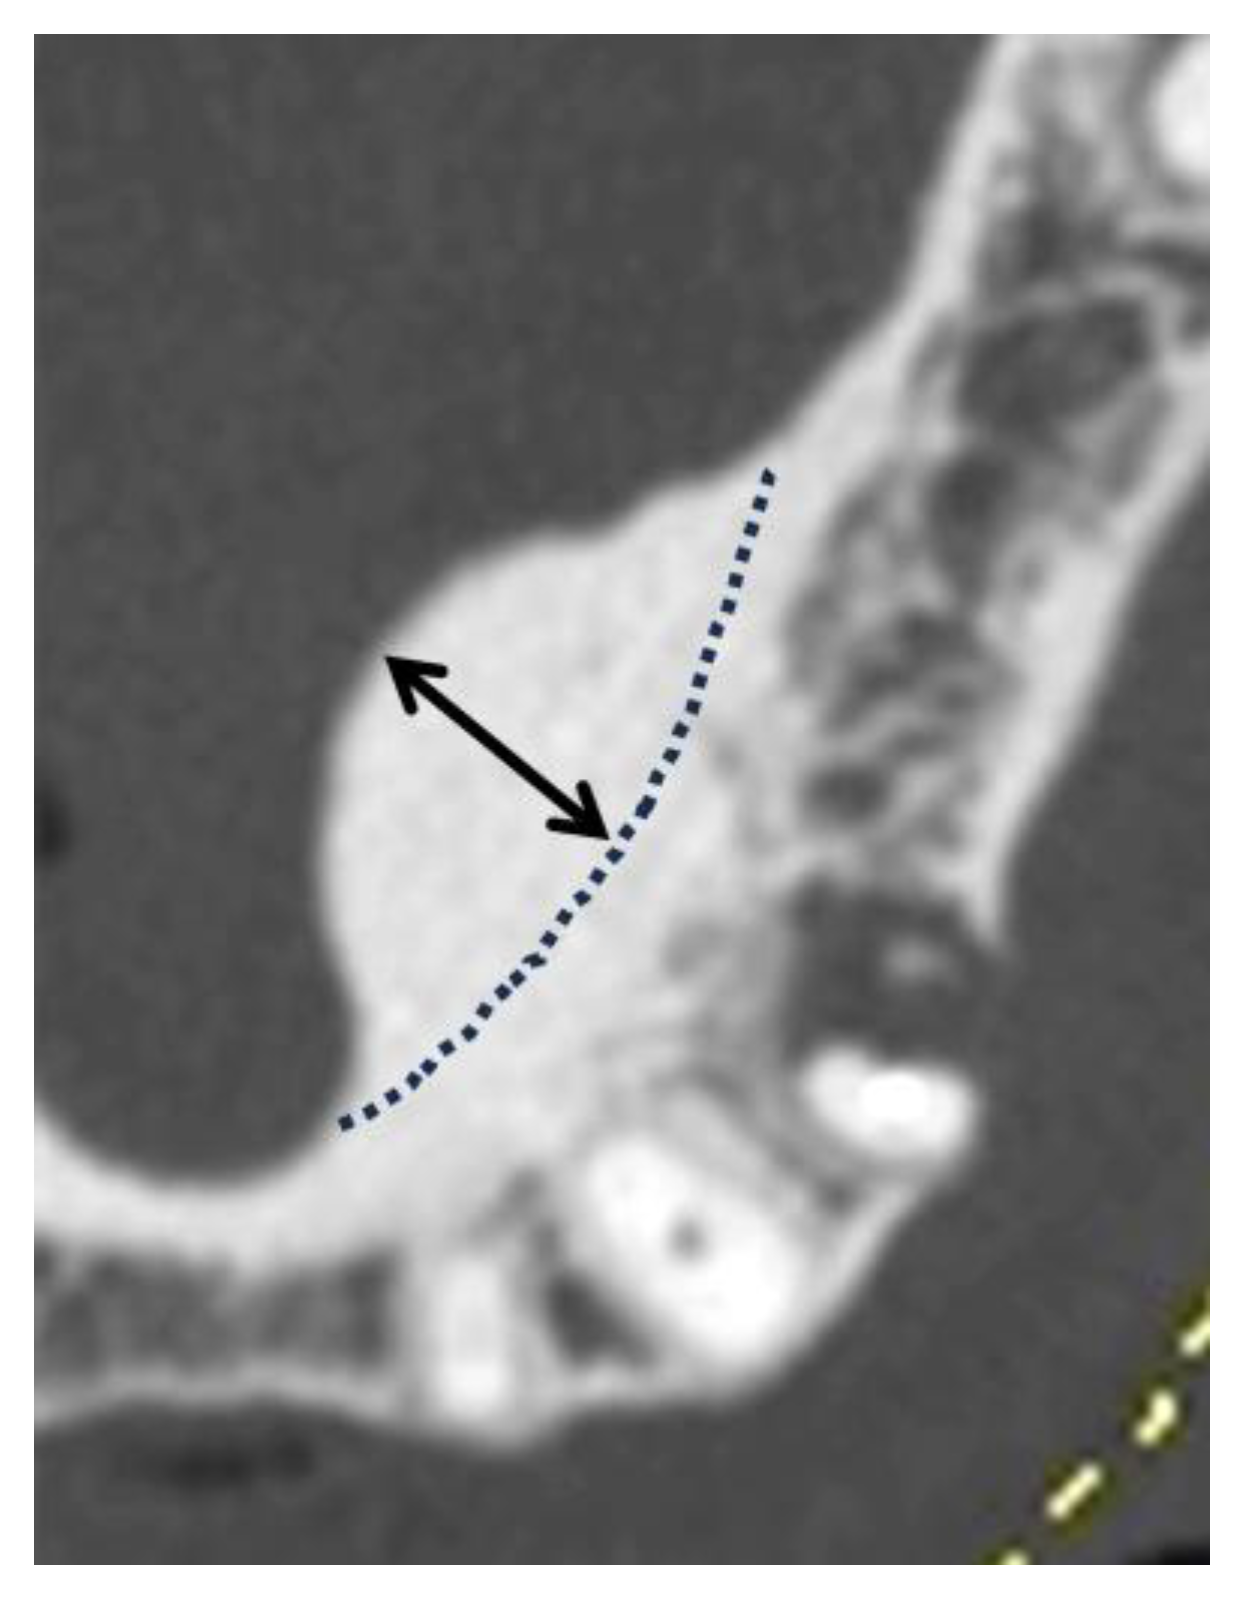

The morphologies of the mandibular tori were classified as types I to IV according to the classification method used in previous studies [1,21,22] (Figure 2). The thickness of the torus was measured from the outline of the normal cortical bone to the crest of the ridge (Figure 3) and was classified into the following categories in accordance with previous studies [17,22,26]: <3 mm, mild; 3–6 mm, moderate; 6 mm or more, severe. When the mandibular torus was polycystic, it was classified on the basis of its thickness.

Figure 3. Measurement points for determining the size of mandibular tori. The distance from the outline of the normal cortical bone (represented by the dotted line in the figure) to the point of maximum protrusion (indicated by the double-headed arrow) was measured. This distance is defined as the size of mandibular tori.